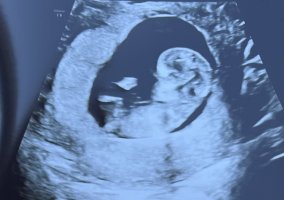

Det er 100% jente. Det der er ikke til å ta feil av.Er 12+3 i dag. Hvilket kjønn tror dere det er ?

Er det bare dårlig ultralydbilder eller er dette fostret veldig ungt? Ser 10-11 uker ut.Tror ikke det er noe synlig her som kan si noe om kjønn, eller?

Har også dette bilde fra uke 13+0Det er 100% jente. Det der er ikke til å ta feil av.

Ble målt til 11+2 der, så er nok en blanding av det og baby som aldri lå roligEr det bare dårlig ultralydbilder eller er dette fostret veldig ungt? Ser 10-11 uker ut.

Ser like jentete ut her!Har også dette bilde fra uke 13+0

Det er for tidlig til å se kjønnBle målt til 11+2 der, så er nok en blanding av det og baby som aldri lå rolig

Ikke mulig å se kjønn så tidlig. Nub må ha mer tid på å utvikle seg. Når er neste ultralyd?Ble målt til 11+2 der, så er nok en blanding av det og baby som aldri lå rolig